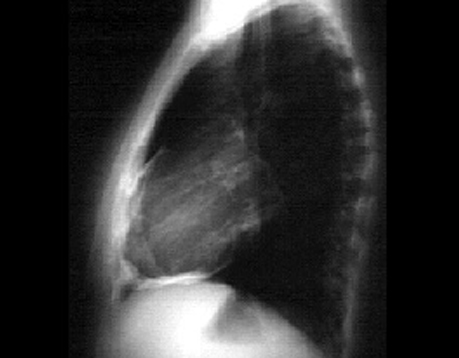

Labs - X Rays

Another Patient's

PA and Lateral

Click on the X rays to enlarge them.

Choose the best interpretation of the chest X rays:

Pericardial effusion

Normal

Lung mass and pericardial effusion

Pericardial calcification

Pericardial cyst